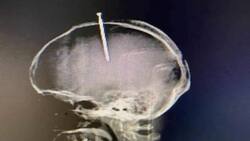

El fentanilo es un fuerte opioide sintético similar a la morfina, que se vende a través de receta médica a pacientes que sufren de dolor crónicos o severos, y para tratar el dolores que pueden dejar las cirugías.

Su efecto es prácticamente inmediato y se estima que es 50 veces más poderoso que la heroína y 100 más que la morfina, señala el Instituto Nacional sobre el Abuso de Drogas en Estados Unidos (NIDA, por sus siglas en inglés). Sus efectos en el cerebro son parecidos a los de la heroína (50 veces más poderoso) y la morfina (100 veces más poderoso), el cual actúa uniéndose a los receptores opioides que se encuentran en áreas del cerebro que controlan el dolor y las emociones.

Después de consumir opioides muchas veces, el cerebro se adapta a la droga y su sensibilidad disminuye, lo que hace que resulte difícil sentir placer con otra cosa que no sea la droga. Entre los efectos inmediatos que produce está: Felicidad extrema, aletargamiento, náuseas, confusión, estreñimiento, sedación, problemas para respirar y pérdida del conocimiento.